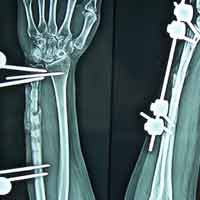

Case:13 Infected nonunion with implant failure

31 years old patient with fracture radius-ulna (1-year-old) with infected non-union was treated with implant removal & external fixation. ‘K’ wiring was done for distal radio-ulna joint stabilization. Bone grafting was done after 3 weeks. Fracture united 6 months’ post-operative.

Pre-Op

Post-op

Imm Post-op

Bone gratfing + ex fix

6 months post-op